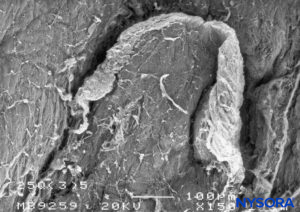

FIGURE 18. Dura-arachnoid lesion produced with 25-G Quincke needle. Epidural surface. Scanning electron microscopy. Magnification ×150. (Reproduced with permission from Reina MA, Castedo J, López A, et al: Cefalea pospuncion dural: Ultraestructura de las lesions durables y abuja’s spindles usages en las punciones lumbers. Rev Arg Anesthesiol. 2008 Jan-Mar 66(1):6-26)

FIGURE 19. Dura-arachnoid lesion produced with 25-G Quincke needle. Arachnoid surface. Scanning electron microscopy. Magnification ×200. (Reproduced with permission from Reina MA, Castedo J, López A. Cefalea pospunción dural: Ultraestructura de las lesiones durales y agujas espinales usadas en las punciones lumbares. Rev Arg Anestesiol. 2008 Jan-Mar 66(1):6-26.)FIGURE 19. Dura-arachnoid lesion produced with 25-G Quincke needle. Arachnoid surface. Scanning electron microscopy. Magnification ×200. (Reproduced with permission from Reina MA, Castedo J, López A. Cefalea pospunción dural: Ultraestructura de las lesiones durales y agujas espinales usadas en las punciones lumbares. Rev Arg Anestesiol. 2008 Jan-Mar 66(1):6-26.)

Piercing the dural sac during a subarachnoid block causes mechanical disruption of both the dura mater and the arachnoid layer. The cross-sectional area of the puncture site produced by a 25-gauge needle is similar regardless of whether the needle has a pencil point or a cutting end. However, the morphology of the lesion varies depending on the design of the needle tip. Pencil-point needles produce a greater and rougher-appearing injury to the dural fibers, while cutting needles produce a U-shaped lesion or flap resembling the open lid of a tin can (Figures 8 to 31).

When using cutting (long bevel) needles, bevel orientation (eg, parallel or perpendicular to the main axis of the cord) does not significantly affect the size or morphology of the lesions in the dura and arachnoid lamina (see Figure 24). The lesion that the needle produces in the dural sac has two components, dural and arachnoid. It is believed that the arachnoid component is vital in limiting cerebrospinal fluid leakage from the subarachnoid space to the epidural space. Therefore, the size and morphology of arachnoid lesions seem to be more important for laminar sealing and cerebrospinal leakage than the size and morphology of dural lacerations.

The incidence of postdural puncture headache (PDPH) has been thought that is affected by the type of needle used (pencil point versus cutting) and of the bevel. The traditional belief that cutting needles result in larger dural lesions (tears) was established in the 1940s and may have been the consequence of the imperfections in the needle design of that era. Modern needles, however, produce clean, U-shaped lesion or flap resembling the open lid of a tin can (see Figure 24).

After needle withdrawal, the U-shaped flap tends to return to its original position due to cerebrospinal fluid pressure and the elastic properties of the dura mater. The dural orifice is almost completely occluded after approximately 15 minutes. On the other hand, lesions produced by pencil-point needles involve a more complex lesion with fiber tearing, sectioning, and separation. The extent of the dural lesion caused by a needle depends on several factors, including the external diameter of the needle, dural and arachnoid sealing mechanisms, needle-tip design, and the quality of needle manufacturing. Needles having the same tip design but different manufacturing methods may not have the same surface quality and may contain microfractures or imperfections, resulting in more or less extensive dural fiber tearing and residual lesions.